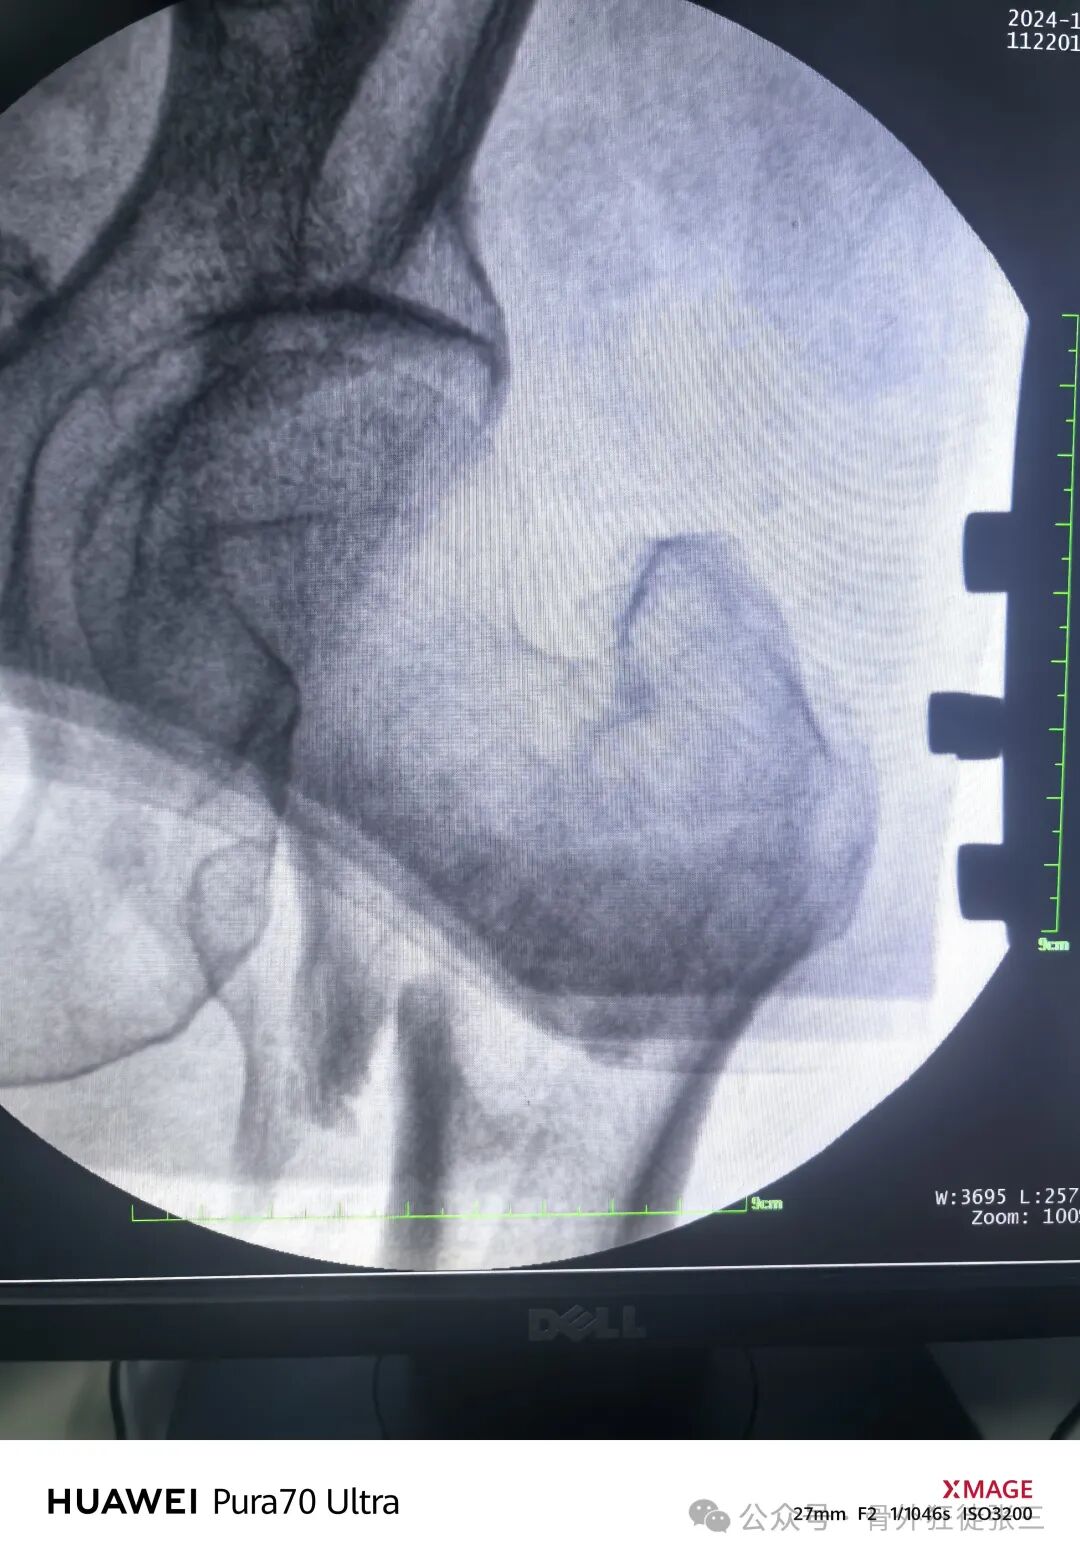

手法复位后透视

正位复位不良

侧位复位欠佳